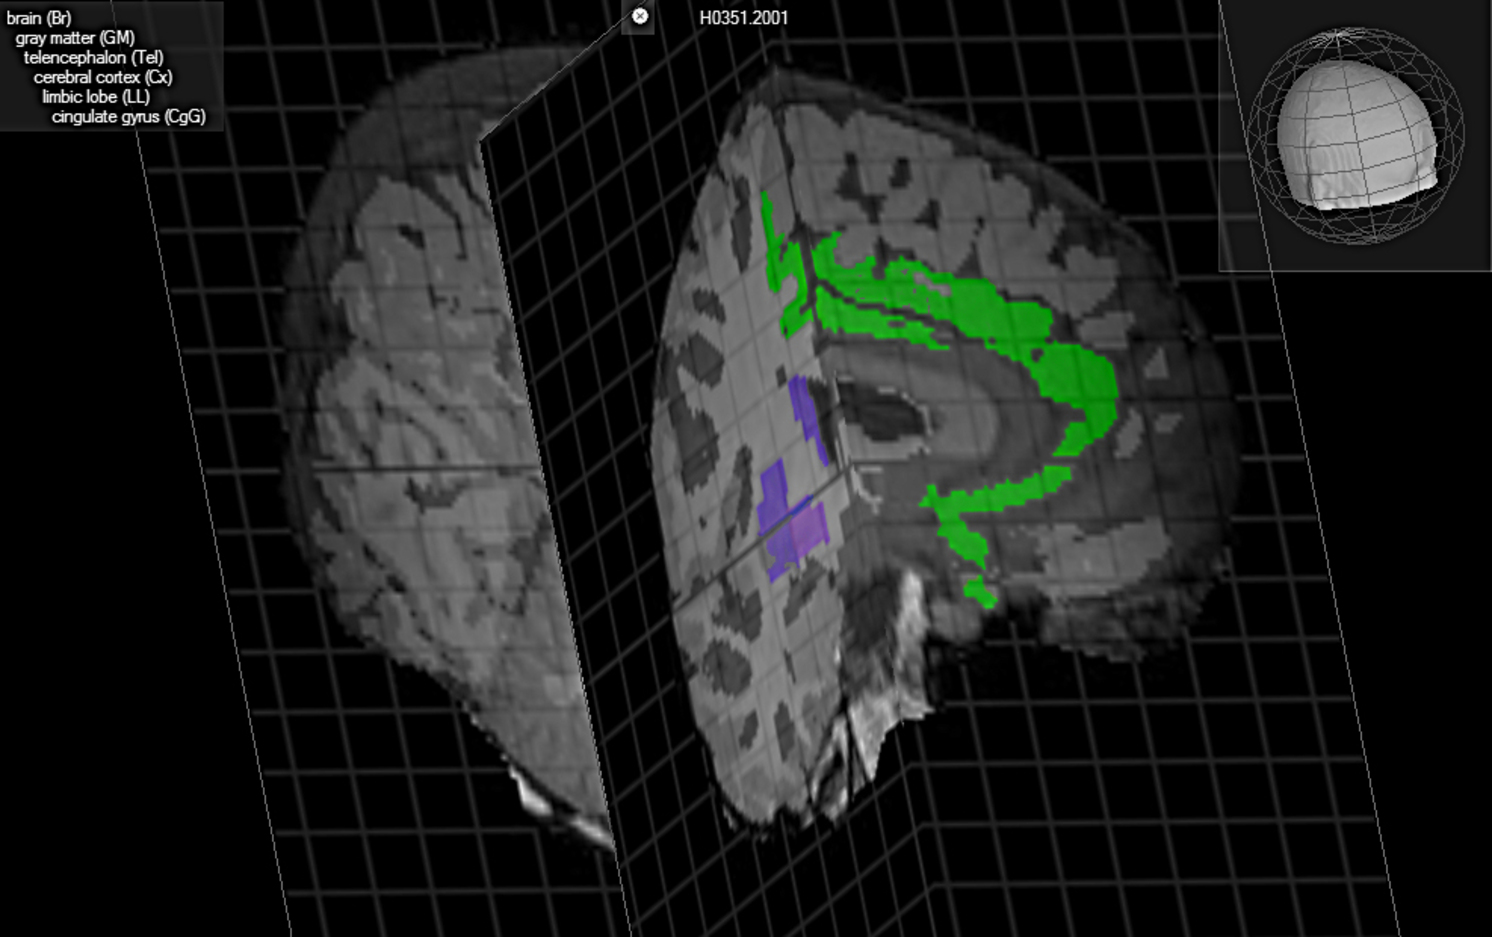

En esta representación del cerebro, aparece en azul la ubicación del claustrum, posible eslabón perdido de la consciencia. Brain Explorer, Allen Institute for Brain Science.